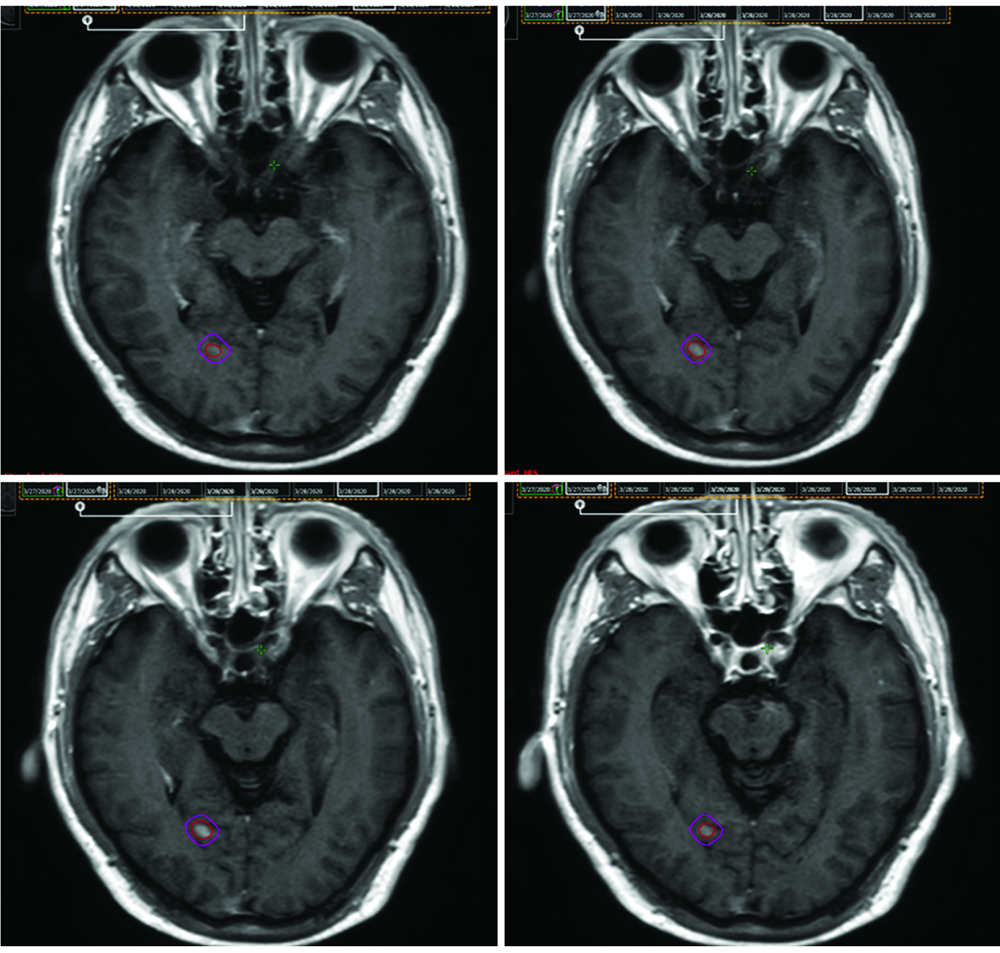

| [2] | 赵永瑞, 高莹, 陈怡东, 徐建堃.基于直线加速器的分次立体定向放疗对小体积脑转移瘤的有效性及安全性[J]. 国际肿瘤学杂志, 2023, 50(3): 138-143. |